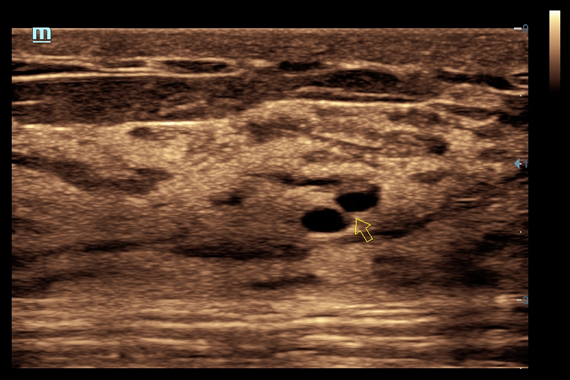

• iNeedle™ - улучшенная визуализация игл при проведении биопсии линейными датчиками

• Nerve package - программы для регионарной анестезии